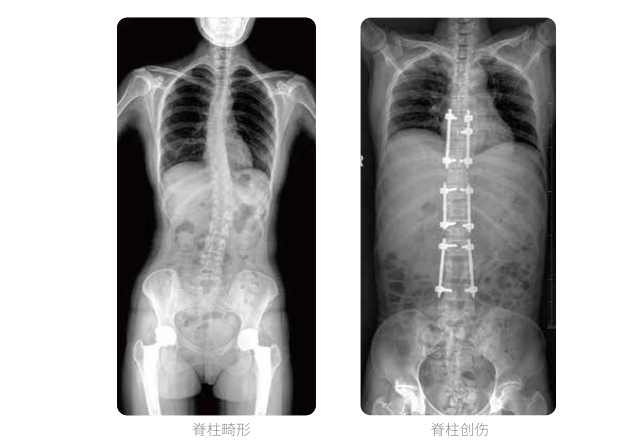

PLX8600大視野平板動態(tài)DR全脊柱一次成像攝片適用于兒童、成人、老年人腰椎退行性病變、強直性脊柱炎、脊柱結(jié)核等臨床應(yīng)用,在此類大視野的臨床拍攝中發(fā)揮了極大的價值。

PLX8600大視野平板動態(tài)DR可在透視情況下多角度觀察病灶部位,做術(shù)前診斷及術(shù)后愈合的檢查,如脊柱斜位透視,可觀察椎弓根峽部,診斷椎體是否滑脫等情況;可在脊柱運動狀態(tài)下通過透視模式觀察全脊柱狀態(tài),了解病變處脊柱的活動度及骨結(jié)構(gòu)的關(guān)系,配合點片功能快速獲得高清的關(guān)鍵幀影像,輔助醫(yī)生制定更準(zhǔn)確的手術(shù)方案。